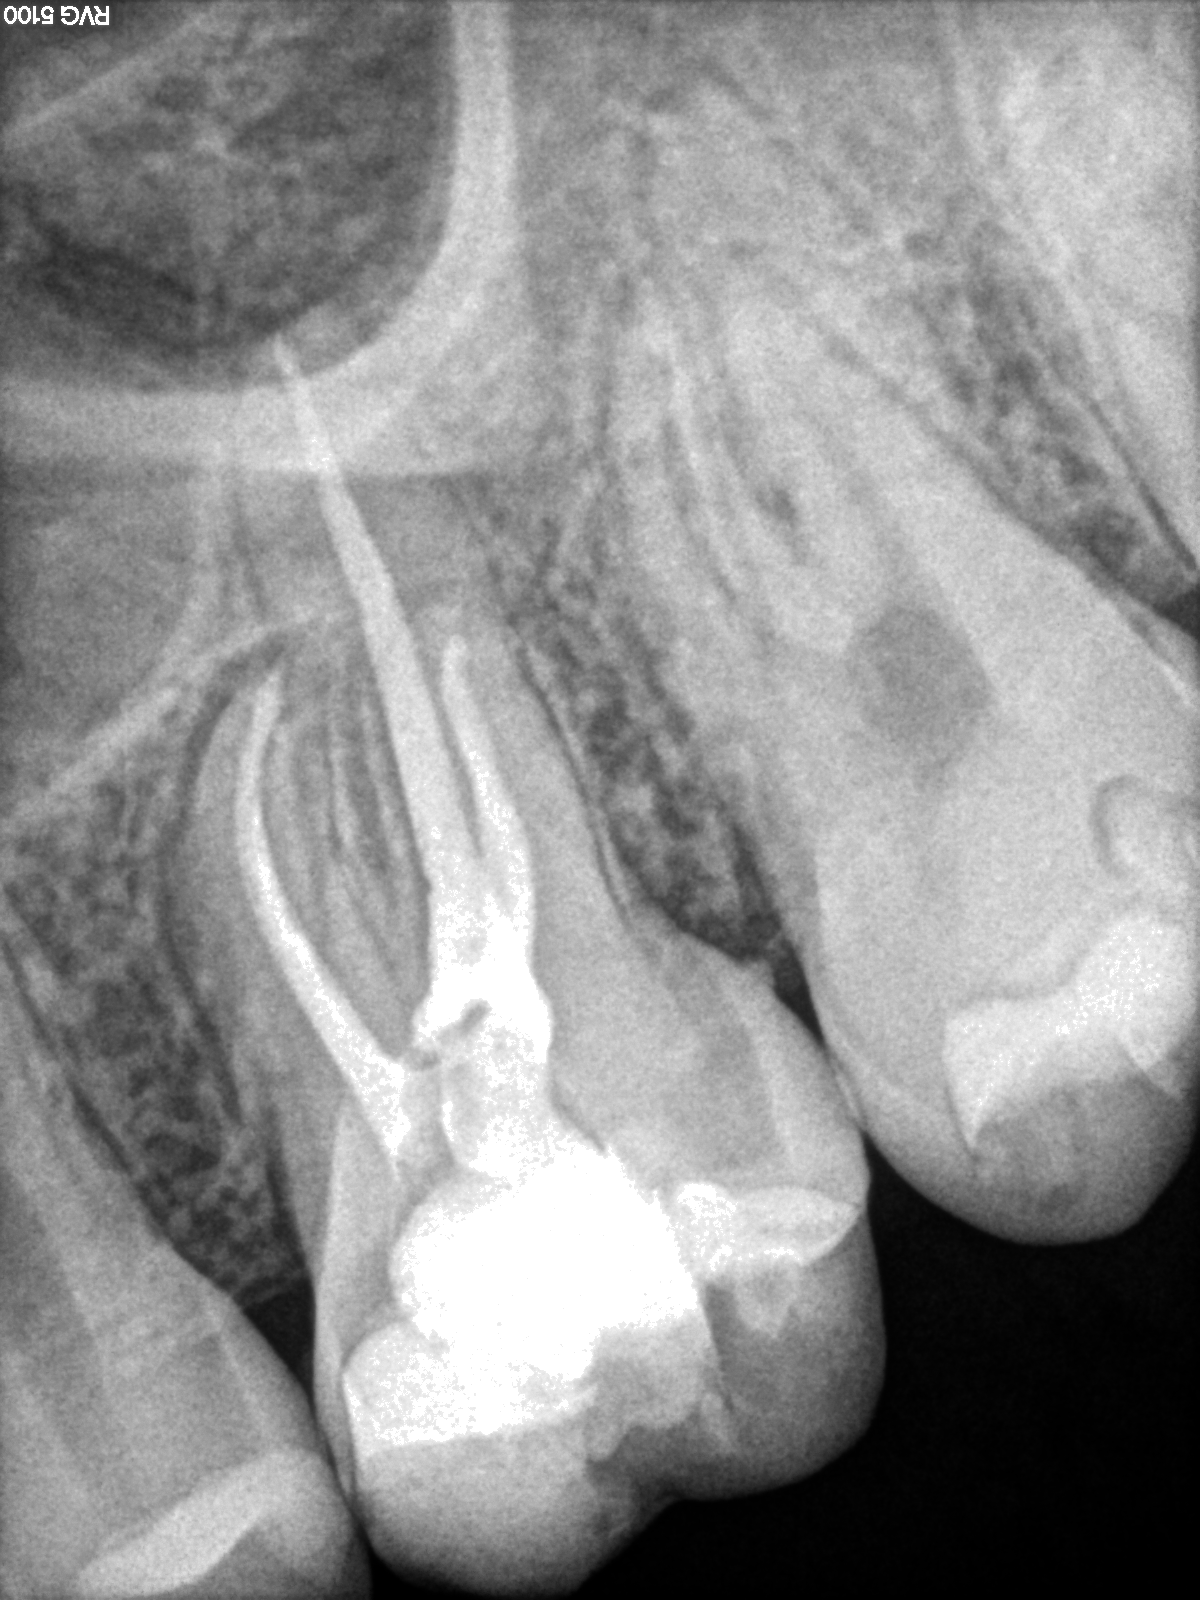

Endodoncia Finalizada Cuatro Conductos